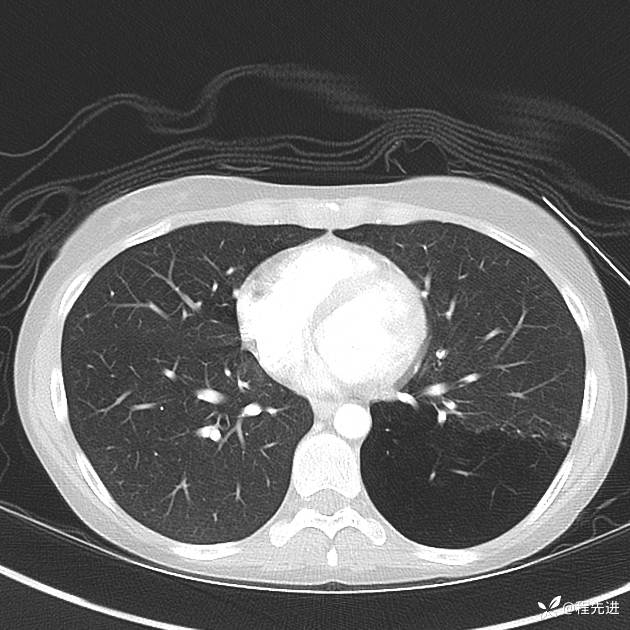

病例【心胸】特别精彩病例|下胸部疼痛3天,这个肺气肿怎么啦

患者性别:女

患者年龄:25岁

简要病史:下胸部疼痛3天

CT增强: